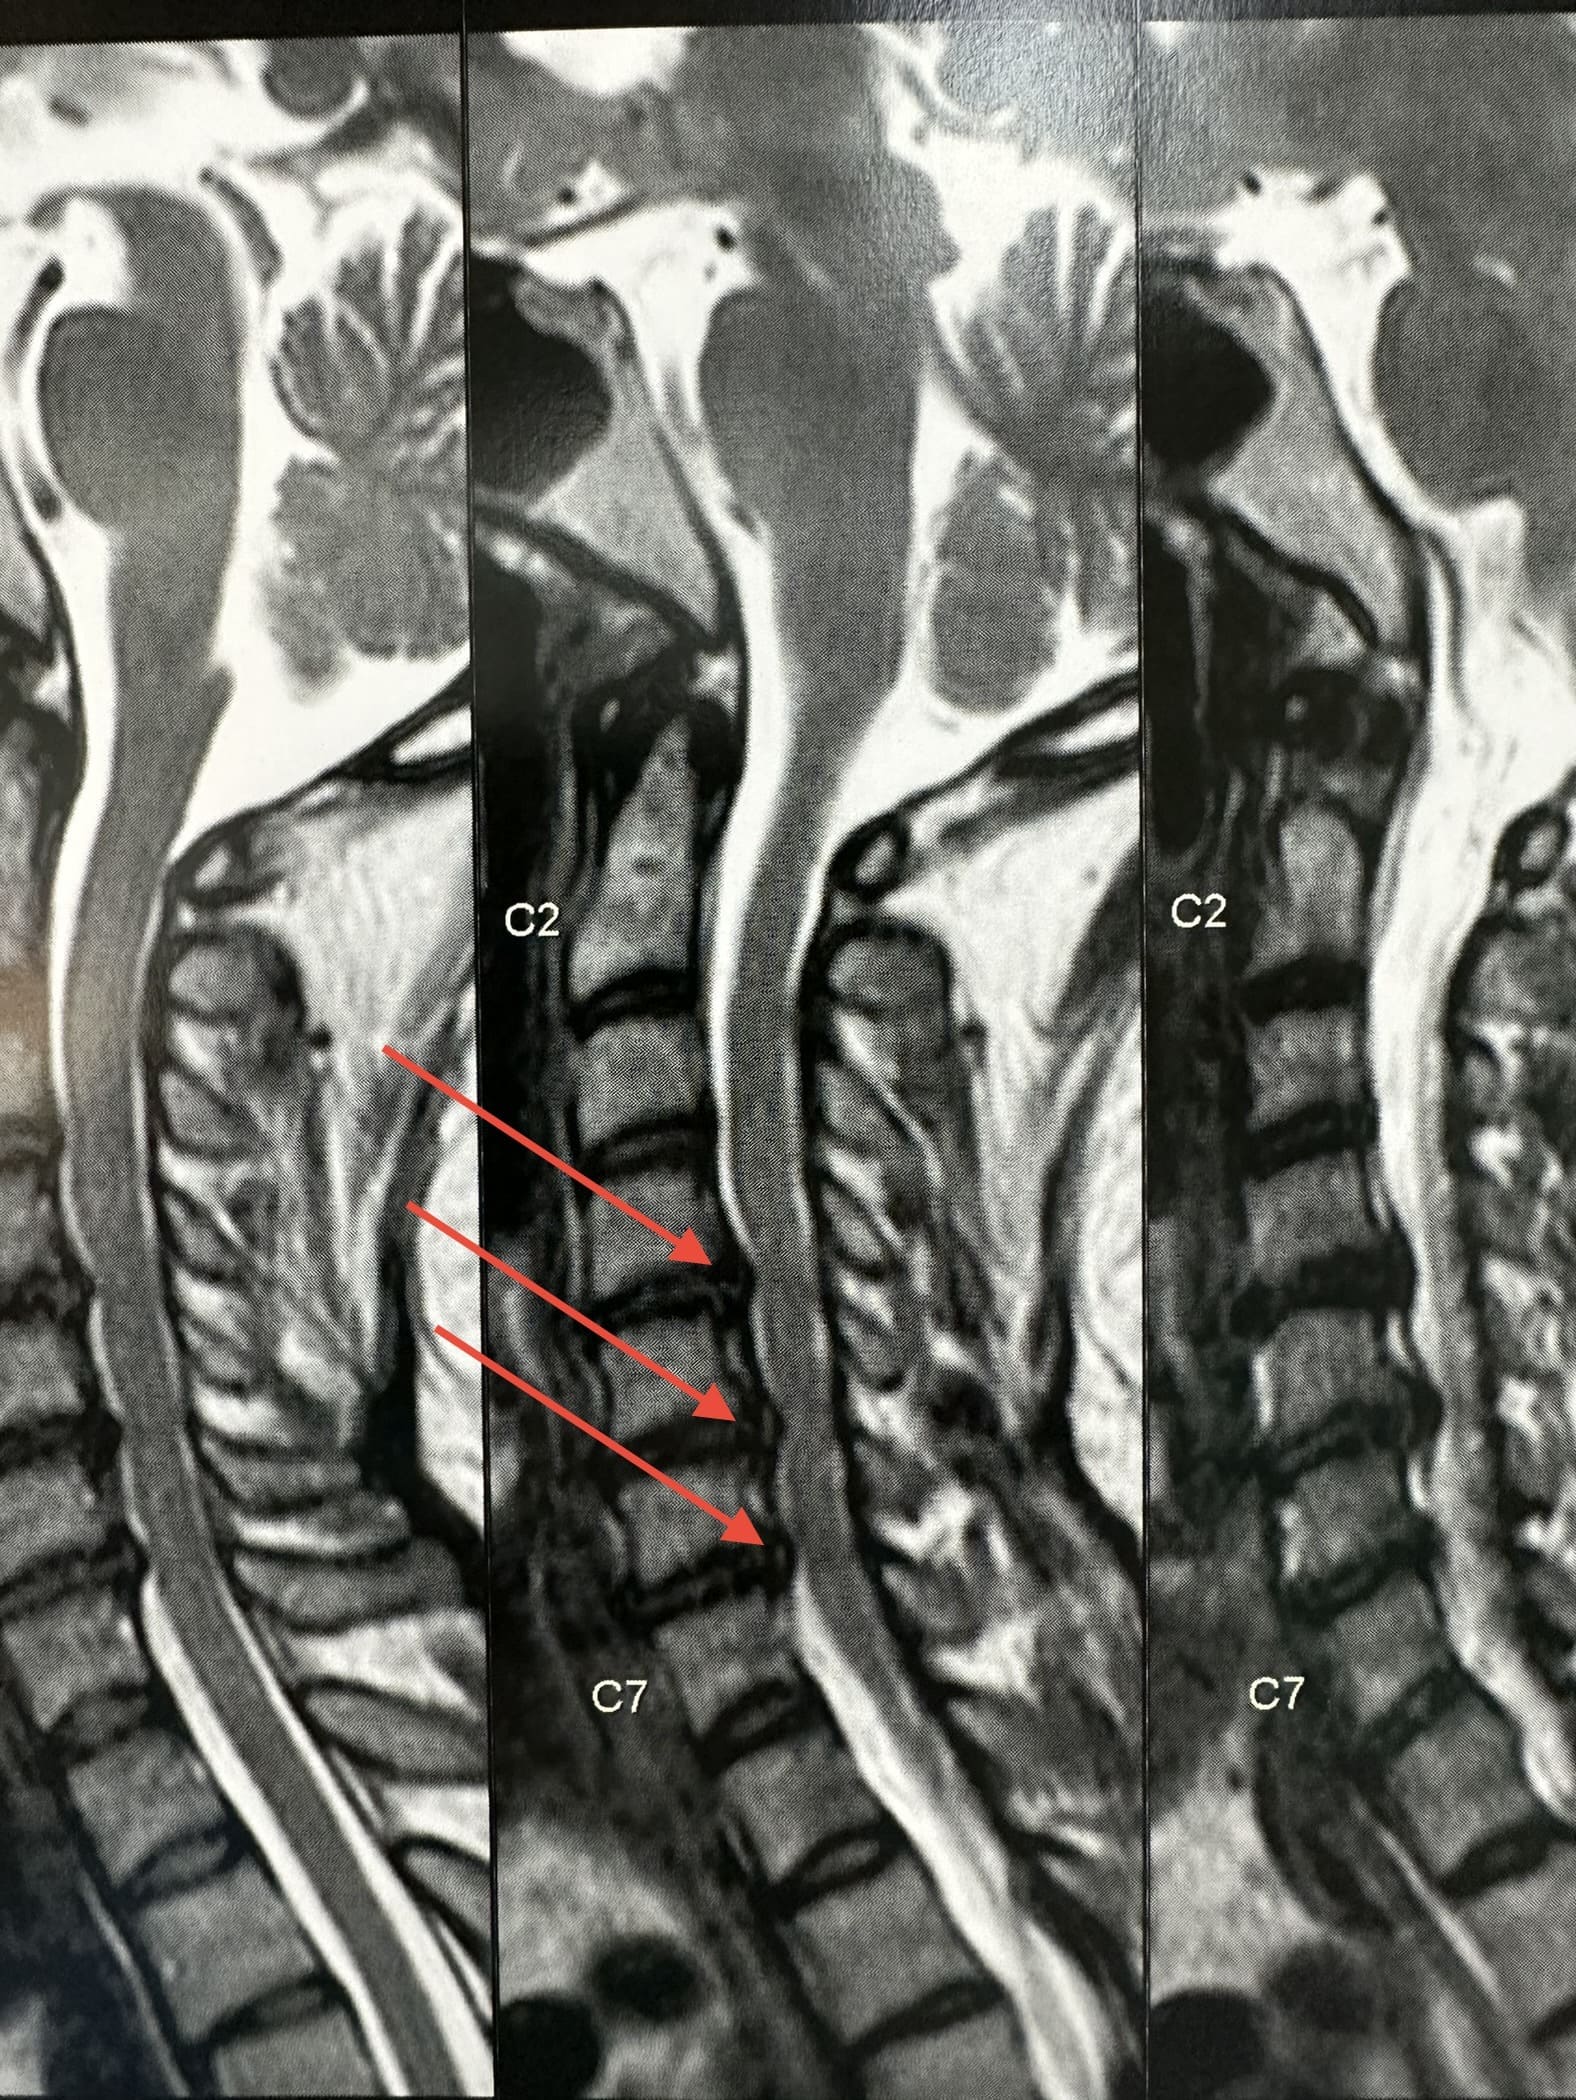

Uma hérnia de disco cervical ocorre quando o material do disco intervertebral se desloca ou se projeta para fora de sua posição normal e comprime as estruturas circundantes, como os nervos ou a medula espinhal.

Exames como ressonância magnética (RM), tomografia computadorizada (TC) e radiografias são frequentemente realizados para diagnosticar a condição da coluna cervical antes de decidir pela cirurgia.